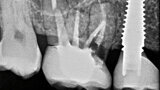

Digitální workflow a aplikace PRF a ozonové terapie v orální rehabilitaci